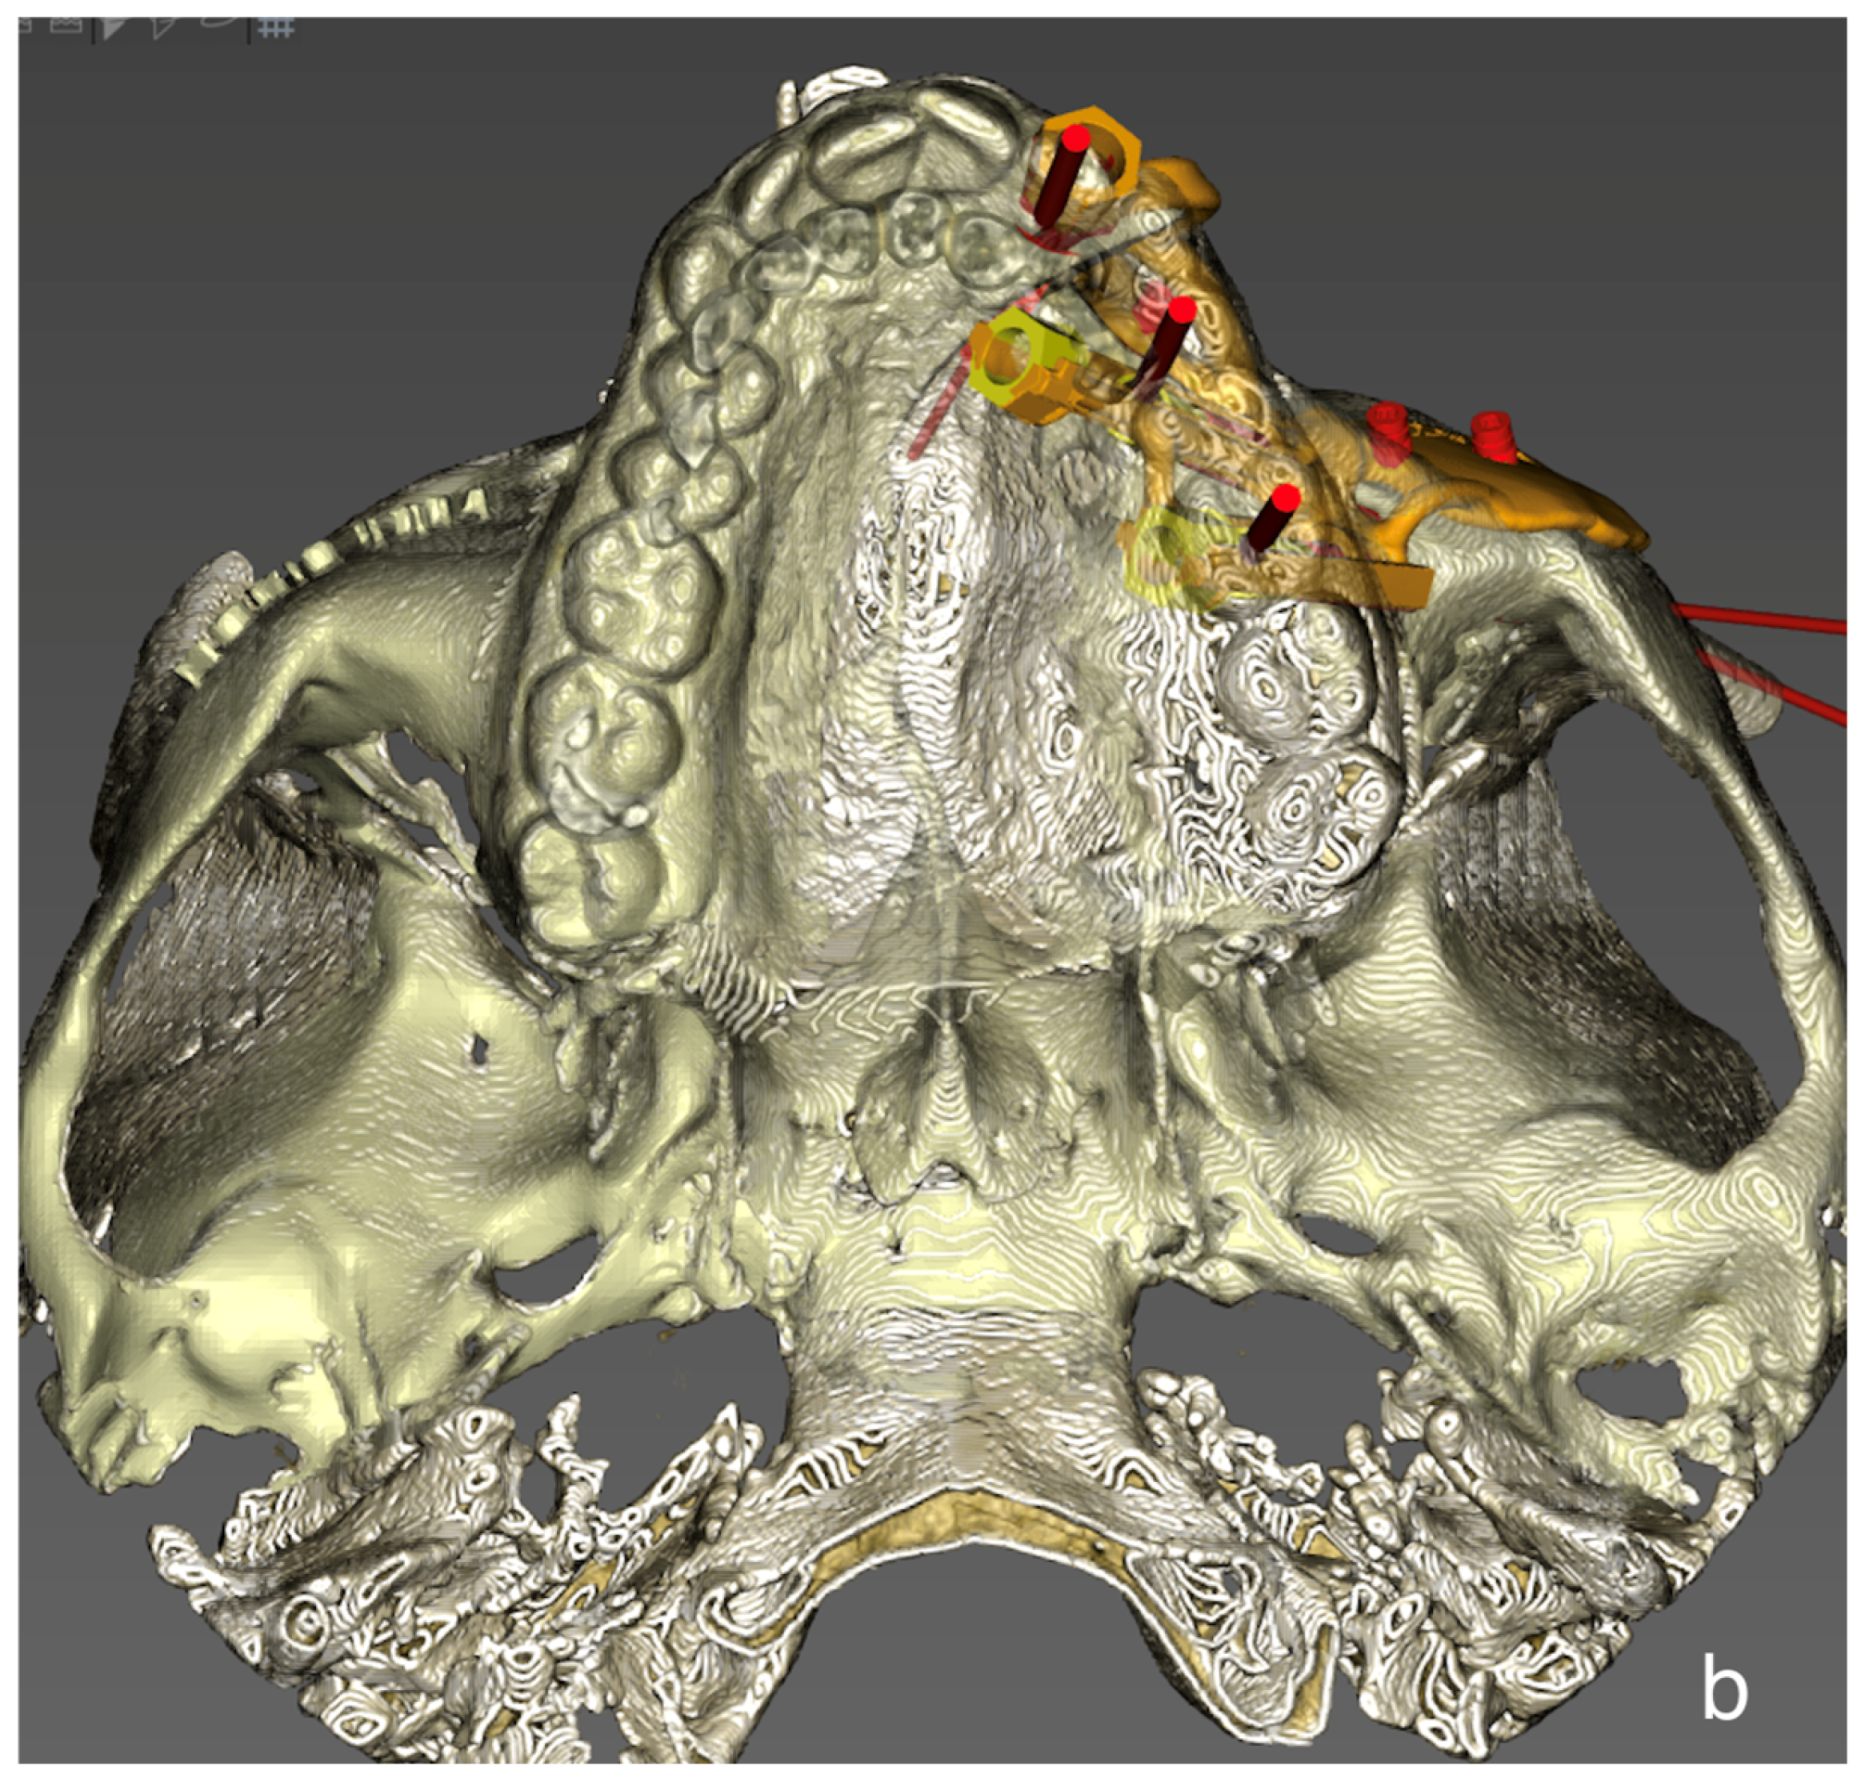

- Implant planning: Using a dental scan of both jaws, plan the positions of zygomatic implants and abutment emergence to fit the dental arch and occlusion. As a guideline, we aim for 15 mm vertical distance between the implant platform and opposing teeth.

- Surgical guide preparation: Plan a surgical guide for both zygomatic and standard implants (Figure 9). Ensure that the guide fits accurately to the post-resection maxillary and zygomatic defect boundaries. We recommend printing a 3D model to help the surgeon visualize the expected surgical defect (Figure 10). For cases with high uncertainty, surgical cutting guides can be printed (though they were not used in this case).